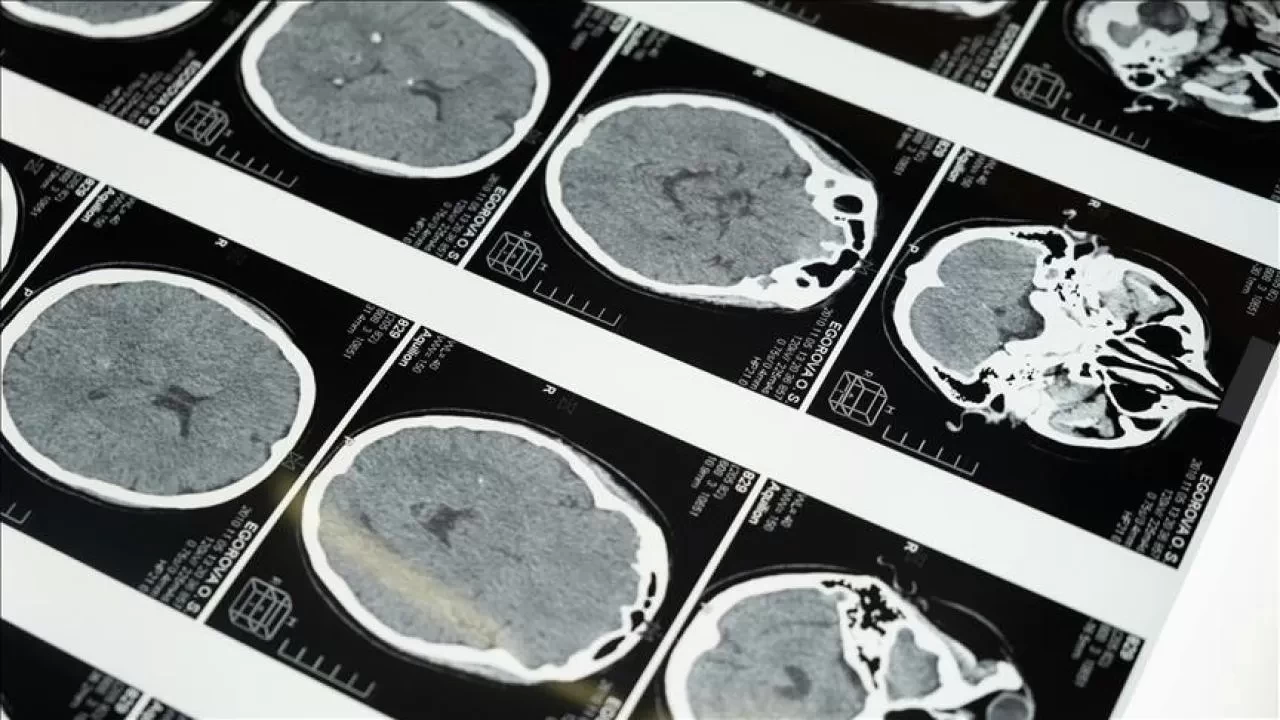

İstanbul'da düzenlenen 1. Dünya Girişimsel Nöroloji ve Nöroşirürji Kongresi'nin (WINNC 2025) düzenleme komitesinde yer alan Eskişehir Osmangazi Üniversitesi Tıp Fakültesi Nöroloji Ana Bilim Dalı Öğretim Üyesi ve İnme Merkezi Sorumlusu Prof. Dr. Atilla Özcan Özdemir, inmenin beyin damarlarının tıkanması (iskemik) ve beyin kanaması şeklinde gelişen iki türünün olduğunu söyledi.

İskemik inmenin dünyada ve Türkiye’de sık görüldüğünü, özellikle kadınlarda görülme sıklığının arttığını ve meme kanserinden daha yaygın hale geldiğini belirten Özdemir, inmenin başlıca ölüm nedenlerinden biri olduğunu ve erişkin yaşta kazanılmış engelliliğin en sık nedeni olması nedeniyle ciddi bir halk sağlığı sorunu haline geldiğini kaydetti.

Prof. Dr. Özdemir, "ileri yaş hastalığı" olarak bilinse de inme görülenlerin ortalamasının 60’lı yaşlara kaydığını, genç yaşta geçirilen inmelerde de artış yaşandığını aktardı.

"Özellikle pıhtıyla tıkanan beyin damarının açılmasıyla ilgili stratejiler gelişti. İnmede erken dönemde yapılan damar açma tedavileri konusunda ülke olarak iyi durumdayız. İnme tedavisinde pıhtıyla tıkalı beyin damarının anjiyo yoluyla açılması mümkün. Böylelikle hastanın 3 ay sonra, 1 yıl sonra kendi işini yapabilecek hale getirilmesi sağlanabiliyor. İnme merkezlerinde uygulanabilen bu işlemi ilk 24 saat içerisinde belirli hasta gruplarına yapabiliyoruz. İlk 24 saat çok kritik, bu müdahaleler de sadece inme merkezlerinde yapılabiliyor."